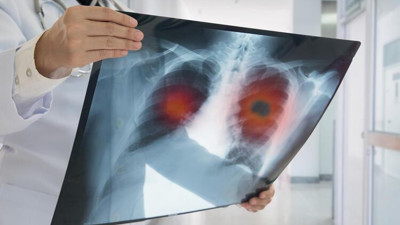

Korona virüsün paramparça ettiği organı açıkladı. Bilim Kurulu Üyesi uyarı üstüne uyarı yaptı Sağlık Bakanlığı Korona virüs Bilim Kurulu Üyesi Doç. Dr. Sema Turan, "Virüsün yarattığı akciğer hasarı inanılmaz. Bir yoğun bakım hekimi olarak söyleyebilirim ki gördüğümüz akciğer filmleri ve tomografileri olayın şiddetinin oldukça fazla olduğunu ve bu hasta gruplarının da zannedildiği gibi çok ileri yaş olmadığını söylemek zorundayım’’ dedi.

Bilim Kurulu Üyesi Özlü: Koronavirüs akciğerlerde kalıcı hasara yol açtı Sağlık Bakanlığı Koronavirüs Bilim Kurulu Üyesi Prof. Dr. Tevfik Özlü, koronavirüsün akciğerlerde kalıcı hasara yol açtığını ve bu nedenle çok sayıda hasta takip ettiklerini belirterek, "Bunların bir kısmı oksijen tüpüne bağlı olarak yaşamak zorunda. Bazılarında ise sürekli oksijen kullanmasalar bile efor kısıtlaması söz konusu" dedi.